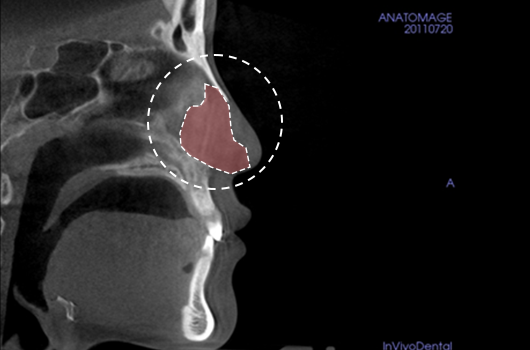

1. Analysis of septal cartilage in various sizes and shapes

Analysis of septal cartilage in various sizes and shapes